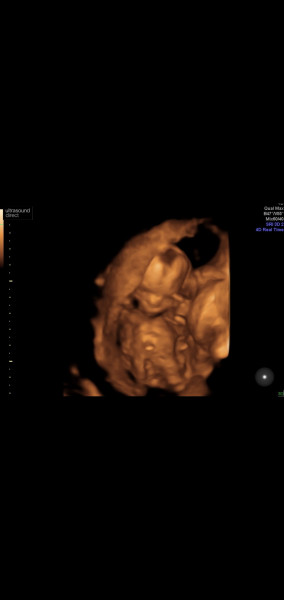

Here's to the nausea, reassurance scans and long waits of the first trimester!